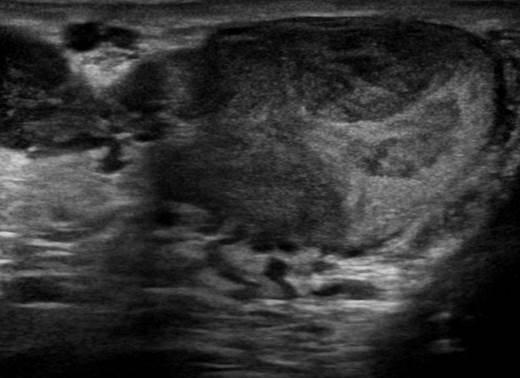

U tinh hoàn

» Thông tin: Nam giới – 35 tuổi.

» Lâm sàng: Sưng tinh hoàn.

# U tinh bào (Seminoma).